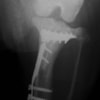

6歳 Mix犬 3.5kg

[主訴]

散歩で駆け出した後にキャンと鳴いてから右後肢を挙上しているとのことで来院。

[検査]

触診検査 MPL左右GradeⅡ

レントゲン検査 にて

右脛骨前方変位あり、ファットパッドサインあり

脛骨公平部角(TPA)の急峻を認める

[治療]

検査結果から前十字靱帯の断裂を疑い脛骨高平部水平化骨切り術(TPLO)を実施することに。また、パテラの安定化のために縫工筋内側広筋切開、滑車溝形成術も併せて実施。

[手術]

前十字靱帯部分断裂

半月板は大きな損傷なし

Fixin T字プレート使用して固定

・術後レントゲン

手術前TPA 28.4° が術後TPA 11.7° に矯正されました。

術後1週間で退院。現在は経過観察中です。

術前TPA計測

手術前

術後TPA計測

手術後

当院ではFixinmicroプレートを使用して小型犬のTPLO手術を実施しております。